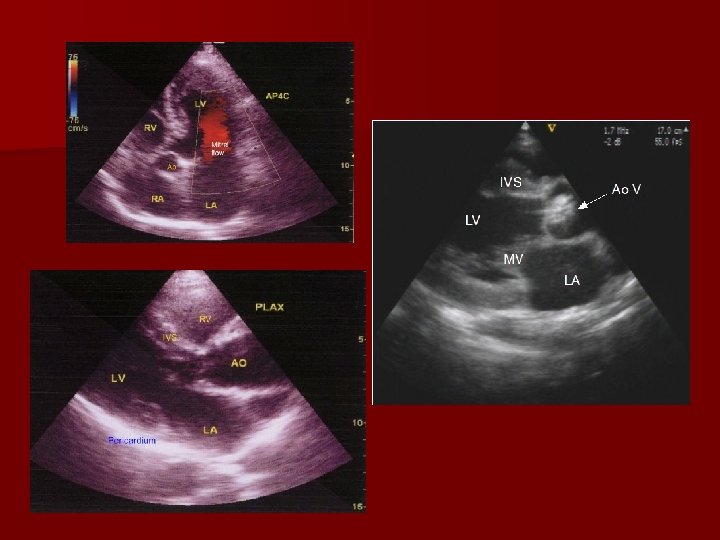

Parasternal Windows: Position the patient in the left lateral decubitus position. The first two windows are taken in the PARASTERNAL window located between the 3 rd-4 th intercostals space. 1)Parasternal Long axis: This image is obtained with the transducer notch facing the right shoulder. In this position the Mitral and aortic valve should be imaged. Pericardial effusions should be assessed.

2) Parasternal short axis: Once the long axis is imaged, the echo probe should be rotated 90 degrees, tilting the probe allows imaging of the left ventricle from the base to the apex. Important aspects and cardiac structures (Aortic and Mitral valves, the IAS and the tricuspid and pulmonic valves) are seen.

Apical Window n Once the parasternal images are obtained, the probe should be placed along the left chest wall at the cardiac apex in the APICAL WINDOW n Apical 2 -Chamber View: n Apical 3 -Chamber View